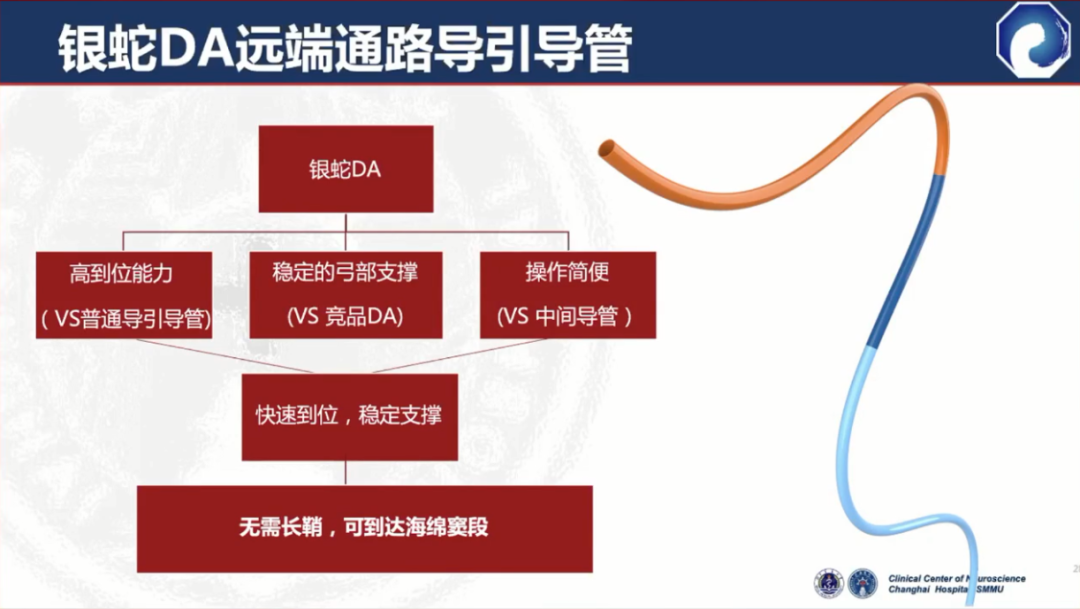

远端通路导引导管既具备传统导管的近端支撑能力,又具备中间导管的远端通过能力

远端柔顺,可达海绵窦段

多功能D型头,超选更容易

一般情况下,无需长鞘辅助

缺点:对于部分II型弓或比较迂曲的血管,弓部和近端支撑力不足

DA XB在DA的基础上做了改进,提升了支撑性

国产新一代远端通路导引导管:通桥银蛇®DA

与竞品DA相比,弓部和近端支撑力更强

40°头端预塑形,主动脉弓超选更容易。0.071大内腔设计,可以兼容多种器械

105cm长度设计,器械出头更容易

通桥医疗银蛇®DA在迂曲血管中也能实现高到位

通桥医疗银蛇®DA设计特点